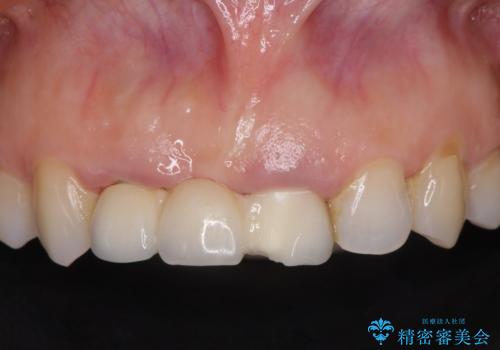

歯周外科をおこなったことで歯ぐきのラインを整え、脱離しないような前歯のブリッジを作製することができました。